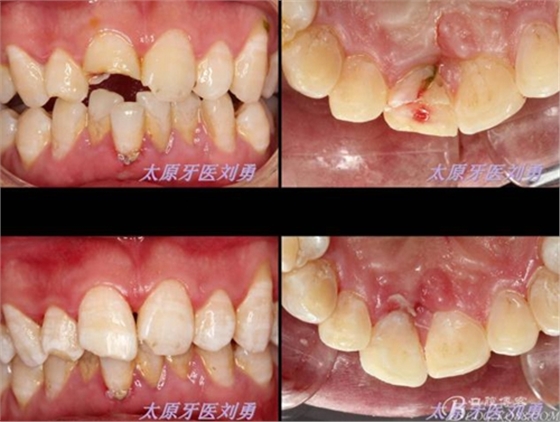

首先為了粘結(jié)斷端,選擇去除牙髓,行一次性根管治療后,首先處理舌側(cè)碎片,圖中可見(jiàn)舌側(cè)碎片裂至齦下,且牙齦有明顯撕裂,如果拔除折裂片,則難以修復(fù),或者選擇牙冠延長(zhǎng)或者選擇即刻種植,本人做了一種嘗試:粘結(jié)舌側(cè)碎片,首先對(duì)位碎片,發(fā)現(xiàn)對(duì)位后非常密合,如果采用全酸蝕粘結(jié)手段,則務(wù)必要掀開(kāi)碎片,則有可能導(dǎo)致出血污染粘結(jié)面,導(dǎo)致粘結(jié)失敗。于是小心謹(jǐn)慎輕微掀開(kāi)碎片,無(wú)滲血,用最小號(hào)毛刷蘸入自酸蝕粘結(jié)劑,然后直接復(fù)位碎片,并且壓緊,讓粘結(jié)劑能均勻擴(kuò)散至斷面深處,光固化。術(shù)畢檢查,碎片粘結(jié)完好。如下圖:

因周末處理該患者,無(wú)法領(lǐng)取纖維樁,于是將切斷的碎片復(fù)位后,從碎片舌側(cè)面制備一隧道直至根管口深處,(想法是注入流體樹(shù)脂形成一個(gè)樹(shù)脂樁加強(qiáng)固位),然后同上病例中所用方法,粘結(jié)固定斷端。如下圖:

第二日復(fù)查,給予樹(shù)脂恢復(fù)A2A1B1切斷缺損。術(shù)后如下圖: